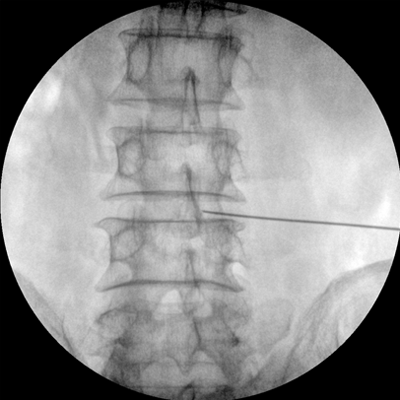

智能化控制系統(tǒng), 讓手術(shù)高效暢捷

四維電動(dòng)運(yùn)動(dòng)控制,平滑定位,使得復(fù)雜角度快速實(shí)現(xiàn)。

專(zhuān)業(yè)的圖像處理系統(tǒng),為您提供高分辨率、高灰階圖像。